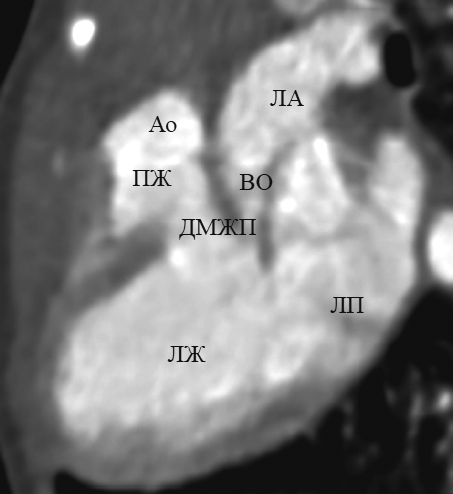

В данной статье приведены результаты анализа данных рентгеновской компьютерной томографии с внутривенным болюсным введением контрастного вещества детей с транспозицией и корригированной транспозицией магистральных артерий путем последовательного построения многоплоскостных реформаций, ориентированных на оси сердца. Из 148 детей со сложными врожденными пороками сердца и магистральных артерий транспозиция магистральных сосудов встречалась у 13 пациентов (в возрасте от 1 до 144 дней жизни; 9 — мужского пола, 4 — женского пола), корригированная транспозиция магистральных сосудов — у 4 пациентов (в возрасте от 6 мес. до 15 лет 6 мес.; 2 — мужского пола, 2 — женского пола). В статье подробно описаны анатомические характеристики, на основе которых определяется морфология каждой камеры сердца, и реформации, в которых они оцениваются. В статье приводится сравнительная характеристика структур сердца и магистральных артерий при транспозиции и корригированной транспозиции магистральных артерий в каждой отдельно взятой реформации, ориентированной на оси сердца. По результатам анализа последовательно построенных реформаций, ориентированных на оси сердца, указаны и проиллюстрированы характерные анатомические признаки транспозиции и корригированной транспозиции магистральных сосудов. Установлено, что из перечня предлагаемых реформаций, ориентированных на оси сердца, характерные анатомические признаки транспозиций достоверно определяются в следующих реформациях: по длинной оси приносящего тракта правого желудочка; левых камер сердца; приточных отделов желудочков; по короткой оси на уровне магистральных сосудов. Многоплоскостные реформации, ориентированные на оси сердца, на основе данных КТ-ангиокардиографии позволяют дать полную и точную анатомическую оценку сердца и магистральных сосудов, что важно при планировании оперативного вмешательства при врожденных пороках сердца.